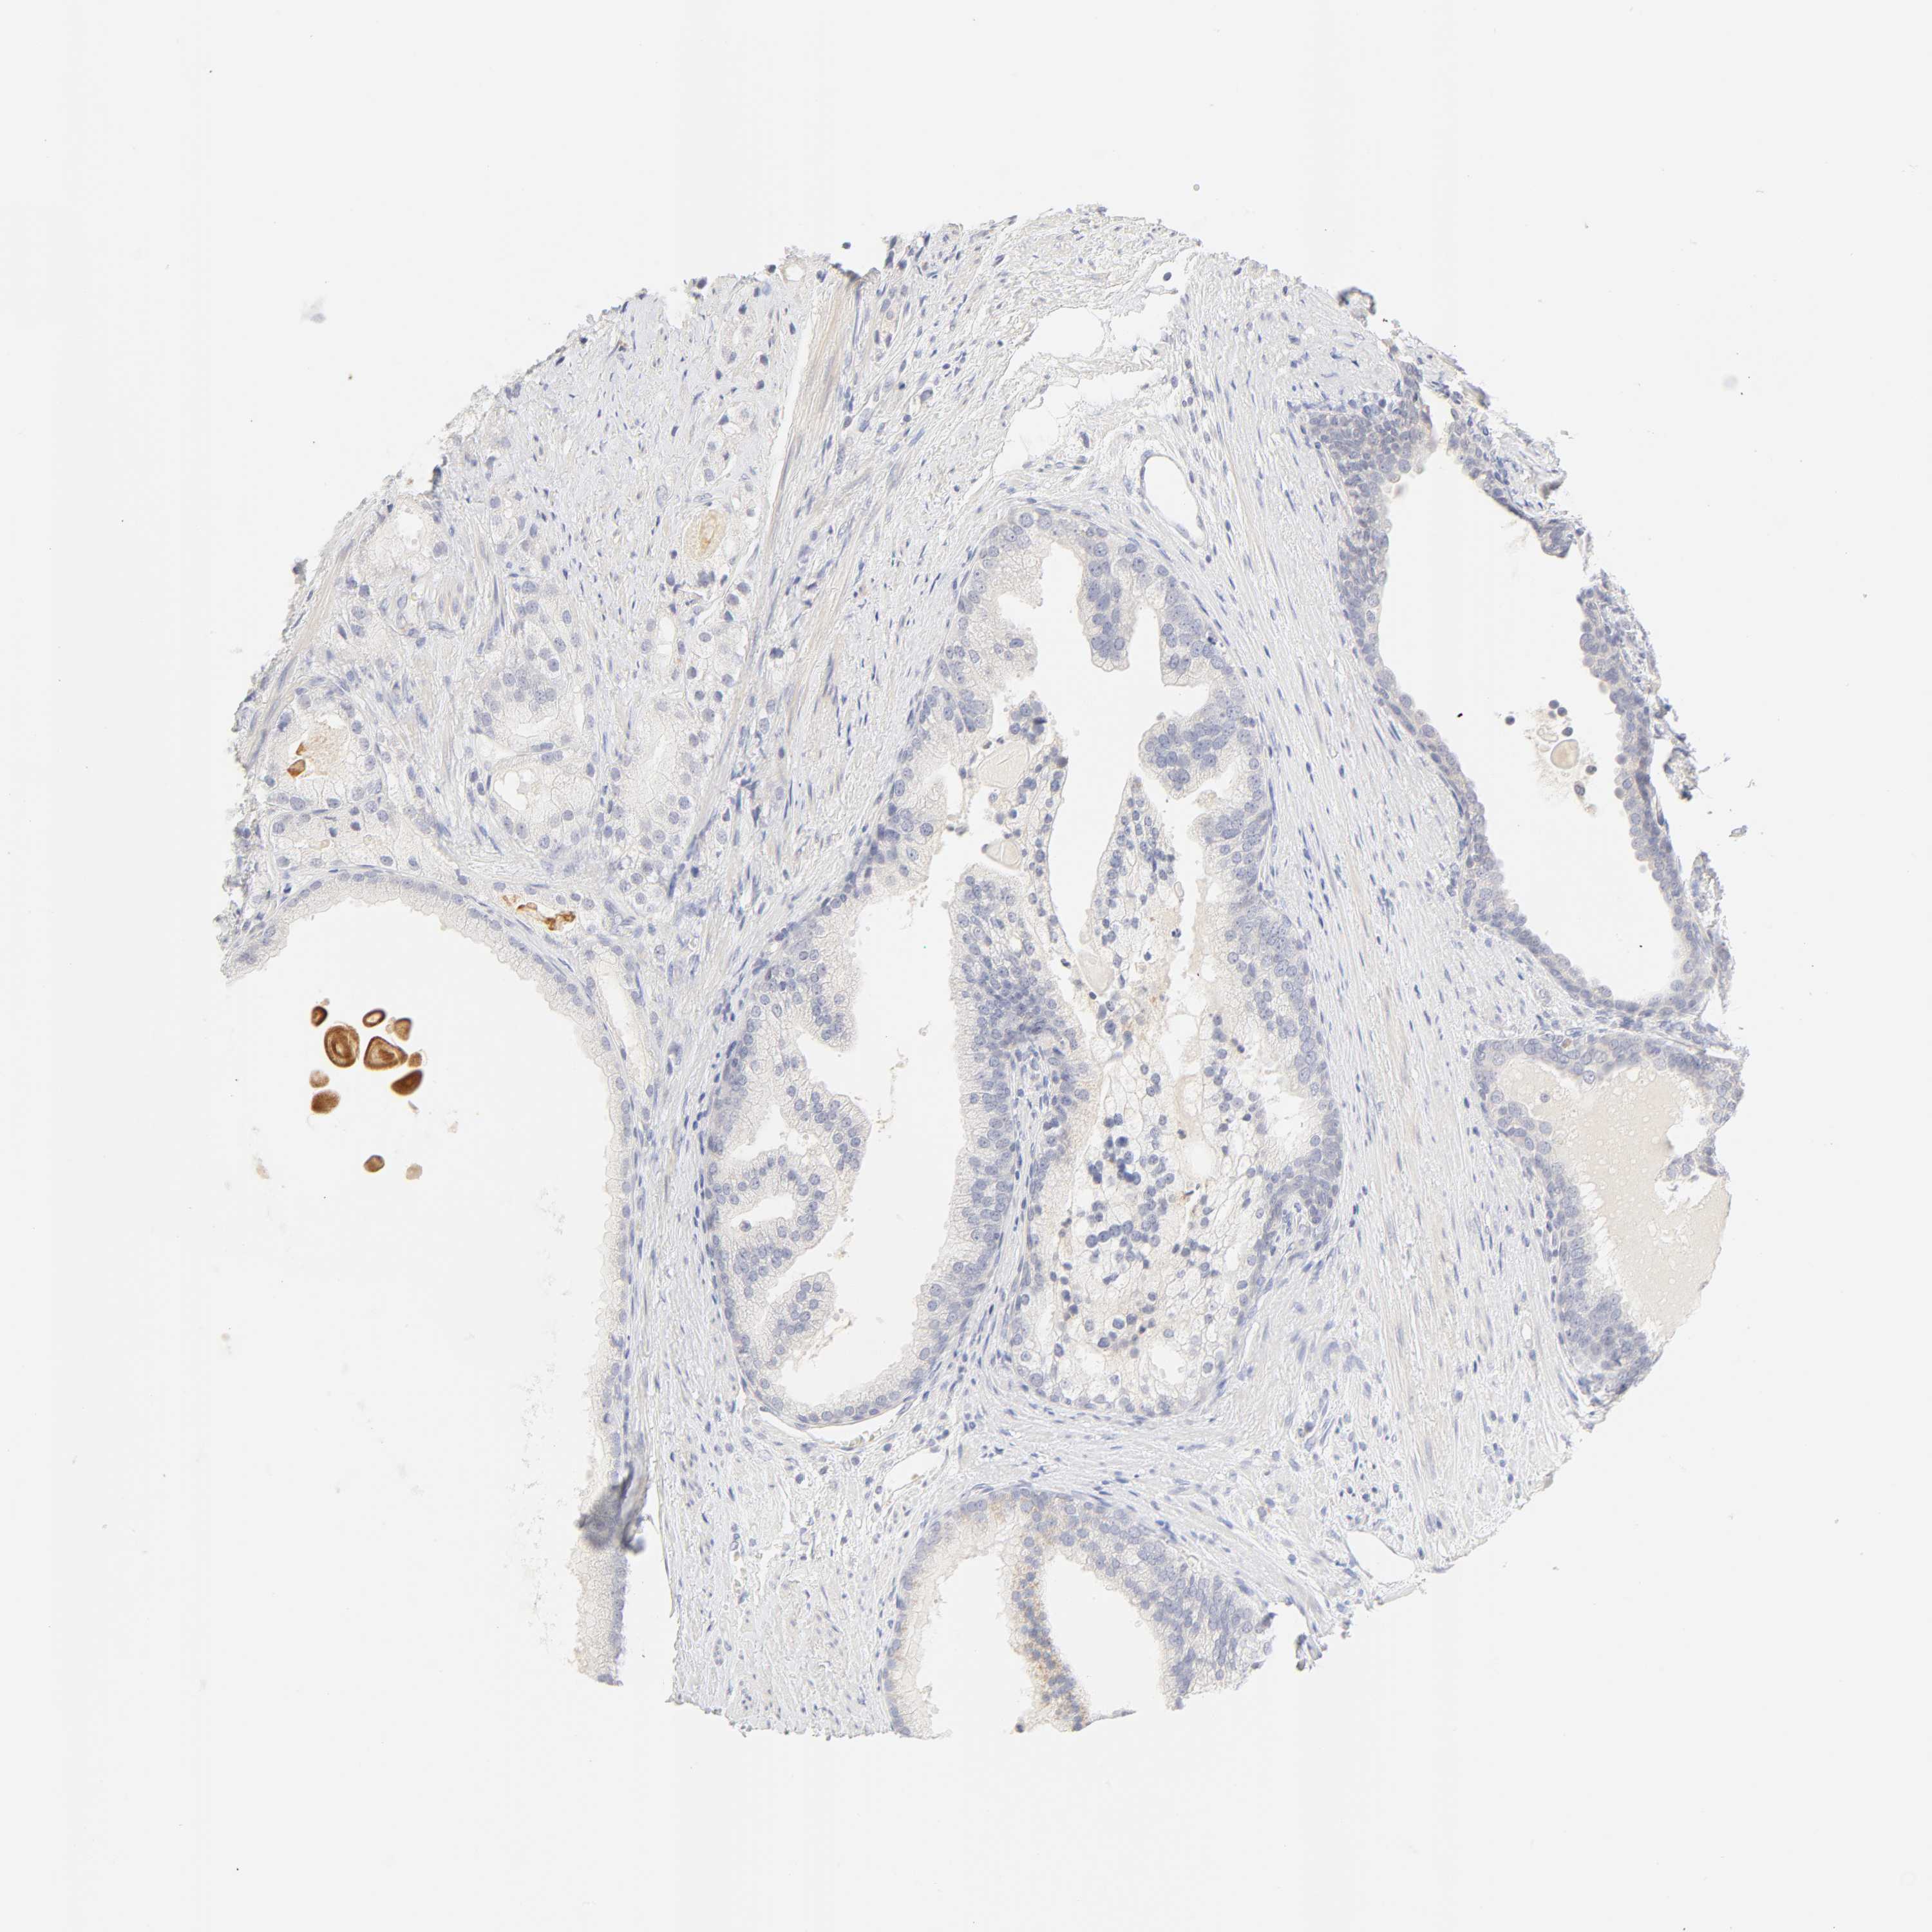

PROSTATE CANCER - Protein expressioni

A mouse-over function shows sample information and annotation data. Click on an image to view it in a full screen mode. Samples can be filtered based on level of antibody staining by selecting one or several of the following categories: high, medium, low and not detected. The assay and annotation is described here.

Note that samples used for immunohistochemistry by the Human Protein Atlas do not correspond to samples in the TCGA dataset.

Antibody stainingi

Antibody staining in the annotated cell types in the current human tissue is reported as not detected, low, medium, or high, based on conventional immunohistochemistry profiling in selected tissues. This score is based on the combination of the staining intensity and fraction of stained cells.

Each image is clickable and will lead to virtual microscopy that enables deeper exploration of all samples and also displays staining intensity scores, fraction scores and subcellular localization as well as patient and tissue information for each sample.

Antibody HPA004331

Staining

High

Medium

Low

Not detected

Intensity

Strong

Moderate

Weak

Negative

Quantity

>75%

75%-25%

<25%

None

Location

Nuclear

Cytoplasmic/membranous

Cytoplasmic/membranous,nuclear

Adenocarcinoma, Low grade

Adenocarcinoma, High grade